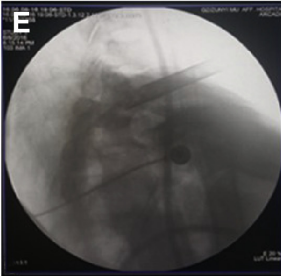

术中C臂透视,可见到达脊髓前方对侧

环钻上骨质,使用c臂确认工作套管位置